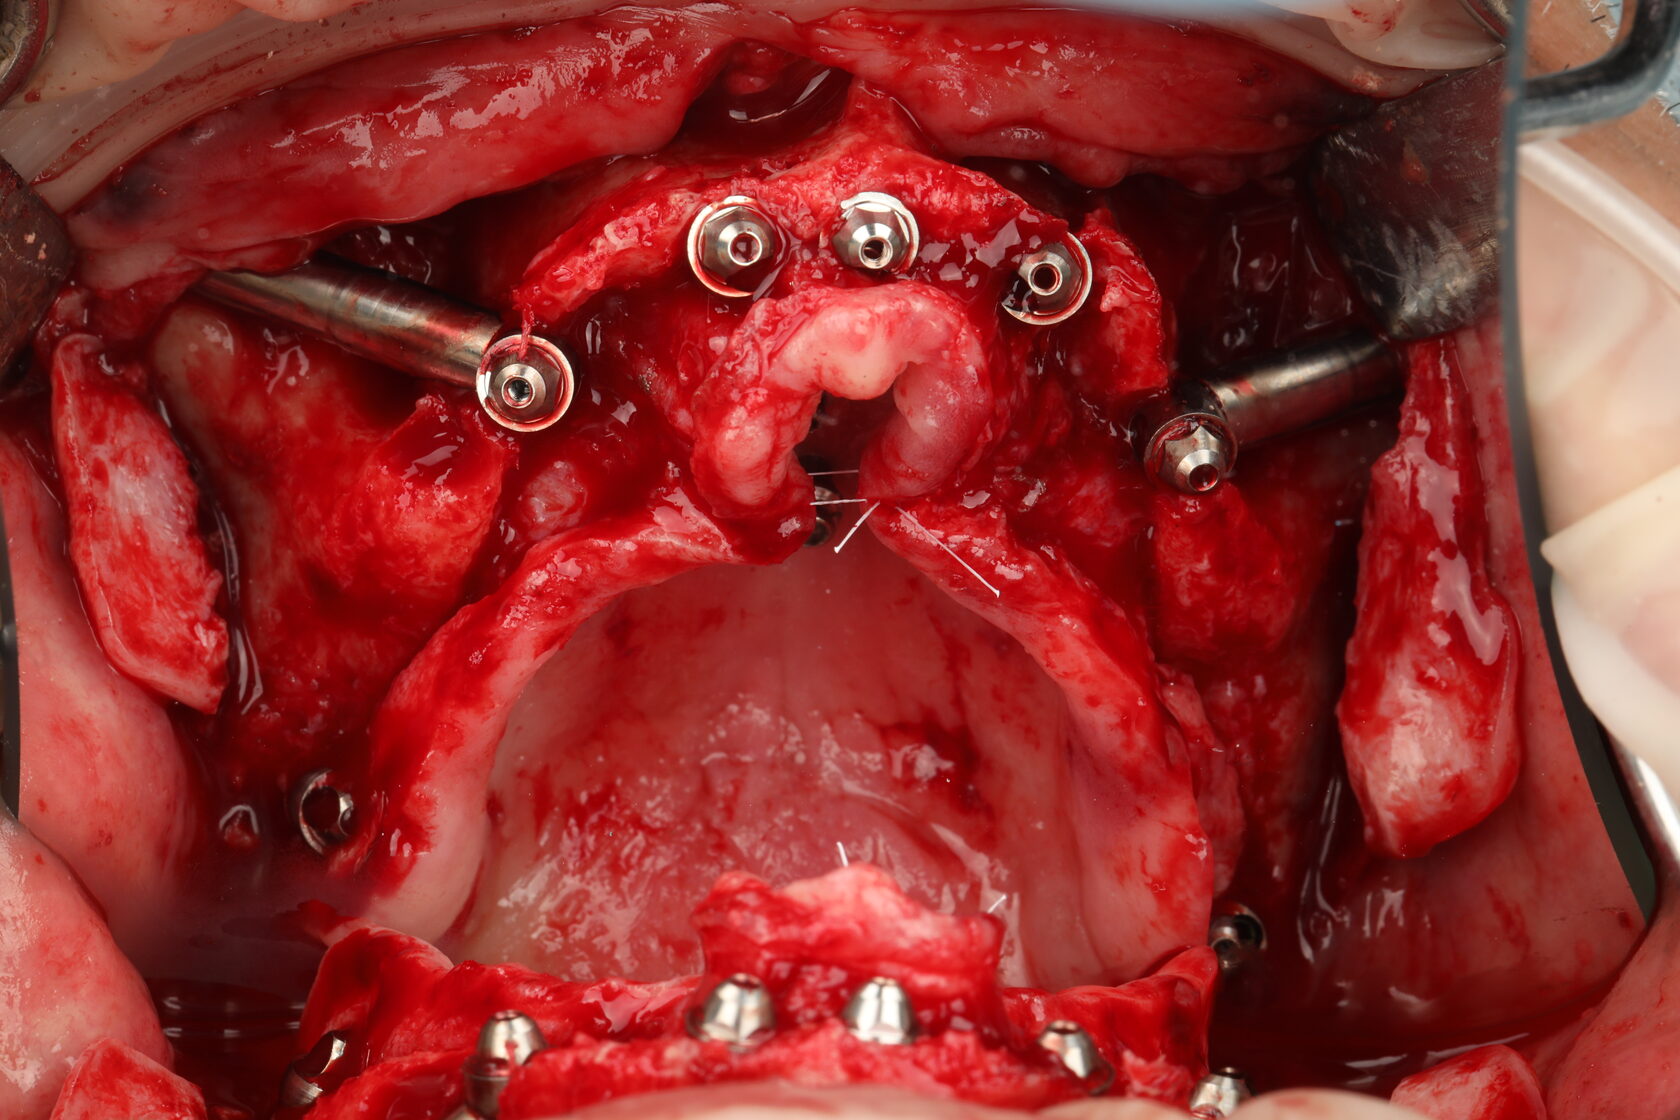

Цифровые протоколы немедленной нагрузки с экстремальной степенью атрофии

От 4 до 6 имплантатов (Maxila on4/ on 5/ on 6) Длинные имплантаты (небный и транссинусальный подход) Скуловые, птеригоидные, назальные имплантаты (транссинусальная, трансназальная постановка)

Разбор Free hands протоколов- итальянская техника от JDental Care! Насо - палатинальная постановка Трансинусальная постановка с фрезами JDNasal Трансназальная постановка с фрезами JDNasal по протоколу Nasa consept Протокол установки скуловых имплантатов anterior/posterior zygomatic по протоколу Zaga concept Трансинусальная и стандартная постановка птеригоидного имплантата Paga Concept

А также разберем техники сканирования с применением авторских палатинальных винтов и сведения сканов, фотограммометрия Tupel 3d (сканирование), граммометрия -truss system